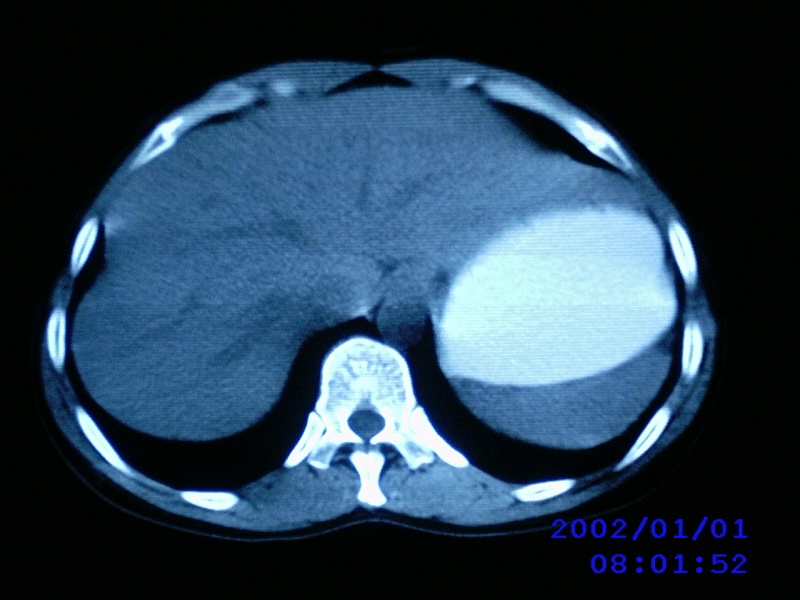

患者,女性,44岁,上腹部疼痛1个多月。b超提示胰头区域有低密度占位性病变。

病人是农村的不愿意做增强,只好麻烦老师们看一下!!

不增强的话价值不大,而且图像没有去色,考虑淋巴瘤可能,胰头病变伴淋巴转移不排除

图片怎么照成蓝色的?看了不太清

把十二指肠挤够呛,支持胰头占位可能----进一步检查。

考虑胰头癌伴肝门淋巴转移

胰头占位,胰管不扩张吗?

考虑胰头癌伴肝门腹主动脉旁淋巴转移

老师病人没有黄疸,没有发烧,只是有点畏寒,中上腹部痛,b超提示胰腺没有问题,只是第二肝门近胰头部见一大小约3.7cmx2.5cm椭圆形低回声,形态欠规则,边界可见.

胰头及其上部见一类圆性软组织占位,密度欠均匀,胆道系统无扩张,胰头钩突部大小正常,胰管无扩张,十二指肠受压---考虑1 肠道间质瘤,不除外胰头无功能腺瘤。